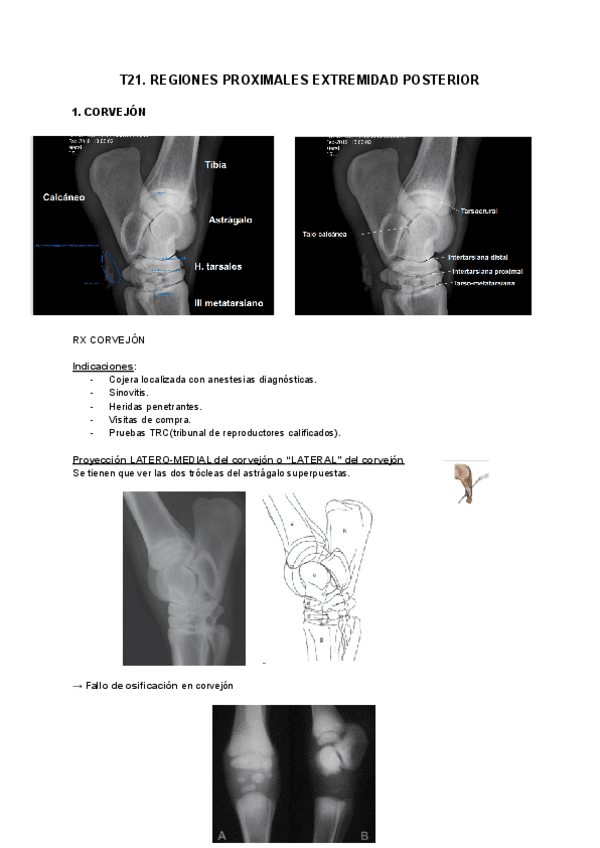

EXT-POSTERIOR-EQUIDOS.pdf

11 páginas